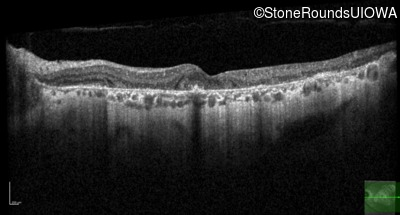

Optical Coherence Tomography - Right - 20/25

Exemplar / OCT Stack

OCT Stack

Optical Coherence Tomography - Left - 20/32 -2